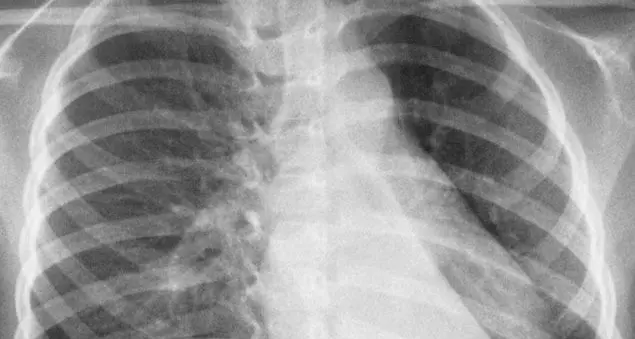

DegenzaDal Vaticano arriva la notizia di una notte serena. La situazione, però, resta critica dopo la crisi respiratoria di ieri mattina e la necessaria trasfusione. In serata atteso un nuovo bollettino medico. Il Pontefice invia a monsignor Fisichella l'omelia da leggere per la messa con i diaconi